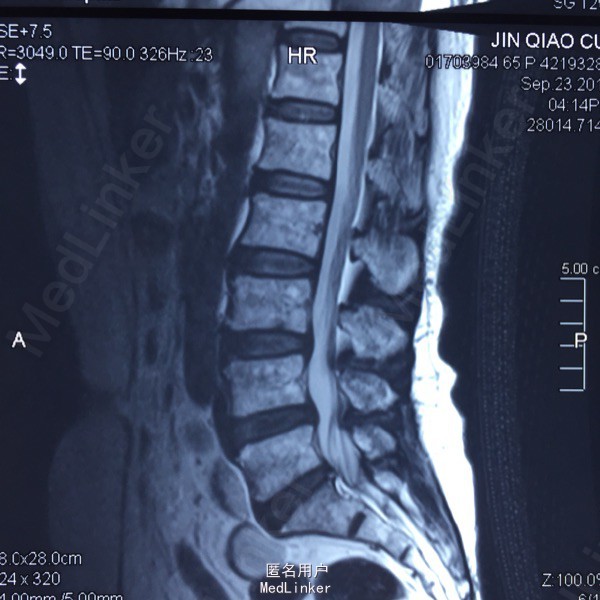

L5-S1左侧棘旁压痛(+),右小腿外侧针刺觉稍弱,右侧跟腱反射稍弱。 腰椎CT提示L5-S1间盘突出,偏右侧。 腰椎X线片提示髂嵴偏高,L5横突肥大。

L5-S1椎间盘突出 C5-6 ACDF术后 拟行椎间孔镜手术

因为穿刺通道比较狭小,进入椎间盘时偏杨氏,采用由内而外的方式减压神经根,用镜下弹性弯钳较好完成了神经根减压。